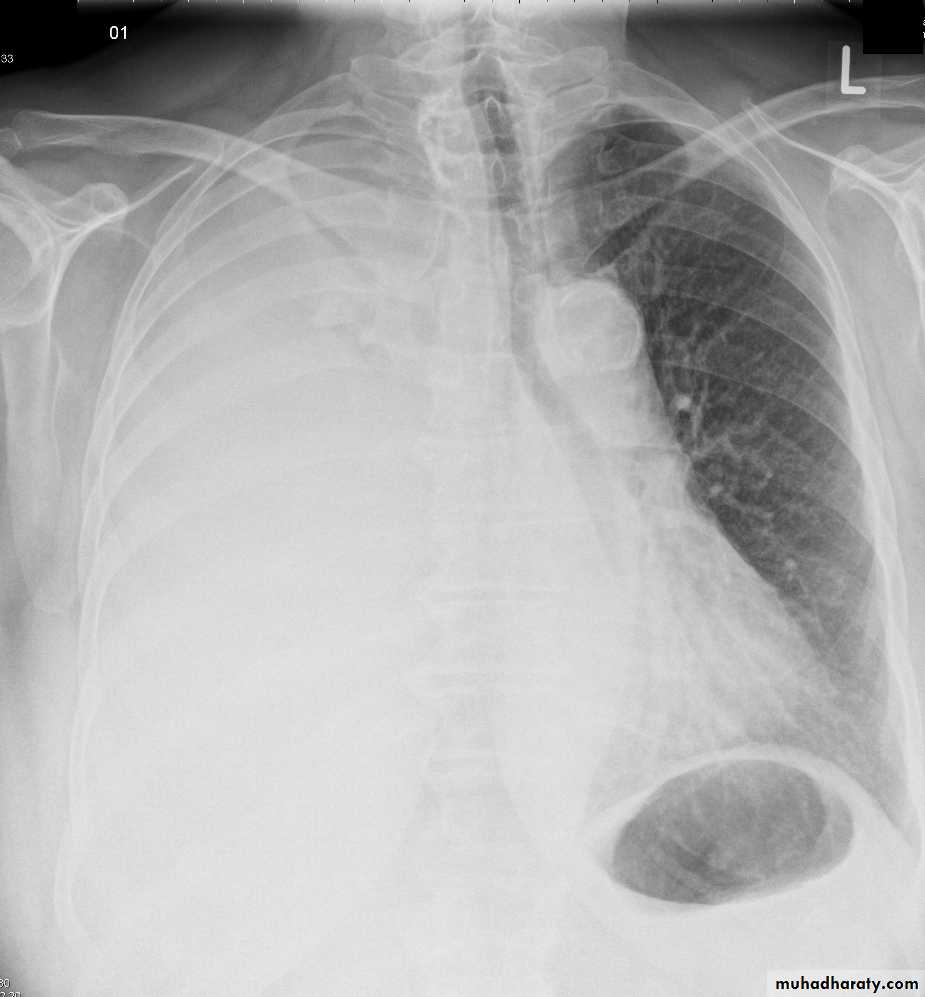

Left lower lobe collapse has distinctive features, and can be readily identified on frontal chest radiographs, provided attention is paid to the normal cardiomediastinal contours. The shadow cast by the heart does however make it harder to see than the right lower lobe collapse

Radiographic features

Left lower lobe collapseis readily identified in a well penetrated film of a patient with normal sized heart, but can be challenging in the typical patient with collapse, namely unwell patients, with portable (AP) often under-penetrated films, often with concomitant cardiomegaly. Features to be observed include :

triangular opacity in the posteromedial aspect of the left lung

edge of collapsed lung may create a 'double cardiac contour'

left hilum will be depressed

loss of the normal left hemidaphgragmatic outline

loss of the outline of the descending aorta

Non-specific signs indicating left sided atelectasis are usually also be present including:

elevation of the hemidiaphragm

crowding of the left sided ribs

shift of the mediastinum to the left

On lateral projection the left hemidiaphragmatic outline is lost posteriorly and the lower thoracic vertebrae appear denser than normal (they are usually more radiolucent than the upper vertebrae) .